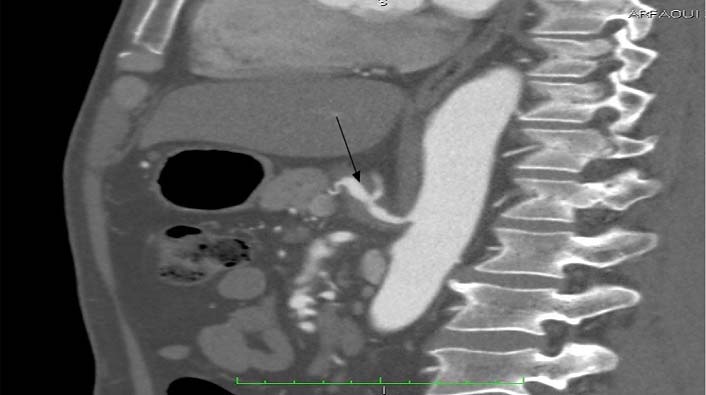

Laboratory data revealed leukocytosis with a white blood cell count of 11,000/ml. There was no evident pathology in the abdominal sonographic examination. An abdominal computed tomography scan with intravenous contrast showed a normal thoraco-abdominal aorta. However, dissection of both the celiac trunk and SMA was determined. SMA dissection was classified as Sakamoto type II b. There was no bowel oedema or free fluid. The dissection of the celiac artery was approximately 22mm long with aneurysmal dilatation [Table/Fig-1,2 and 3] with partial thrombosis causing moderate narrowing.

Abdominal CT scan with intravenous contrast (longitudinal view) reveals an isolated celiac artery dissection (arrow) measuring 22mm in length with aneurysmal dilatation.

Abdominal CT scan with IV contrast (Longitudinal view): demonstrates Celiac artery dissection.